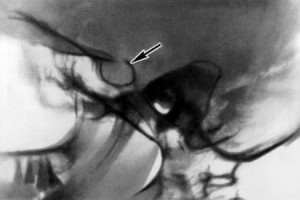

Так называется кость клиновидной формы в черепе человека, напоминающая седло. Спинкой турецкого седла считают костную пластинку, которая его формирует.

Локальная форма. При ней нарушения прочности спинки турецкого седла могут происходить из-за того, что опухоль оказывает давление или в области турецкого седла повышается внутричерепное давление. Когда отмечается остеопороз спинки, то при нем изменения происходят только в проблемной зоне.

Остеопороз турецкого седла — это довольно распространенное осложнение у женщин. Проявляется недуг, как правило, в период менопаузы. Заболевание спинки турецкого седла возникает после удаления матки. При этом часто отмечается поражение головы. Область спинки турецкого седла — это участок головы, который подвержен этому заболеванию. Симптомы разрушения спинки турецкого седла проявляются нарушением костной структуры черепа. Степень разрушения выявляется при помощи рентгеновского снимка.